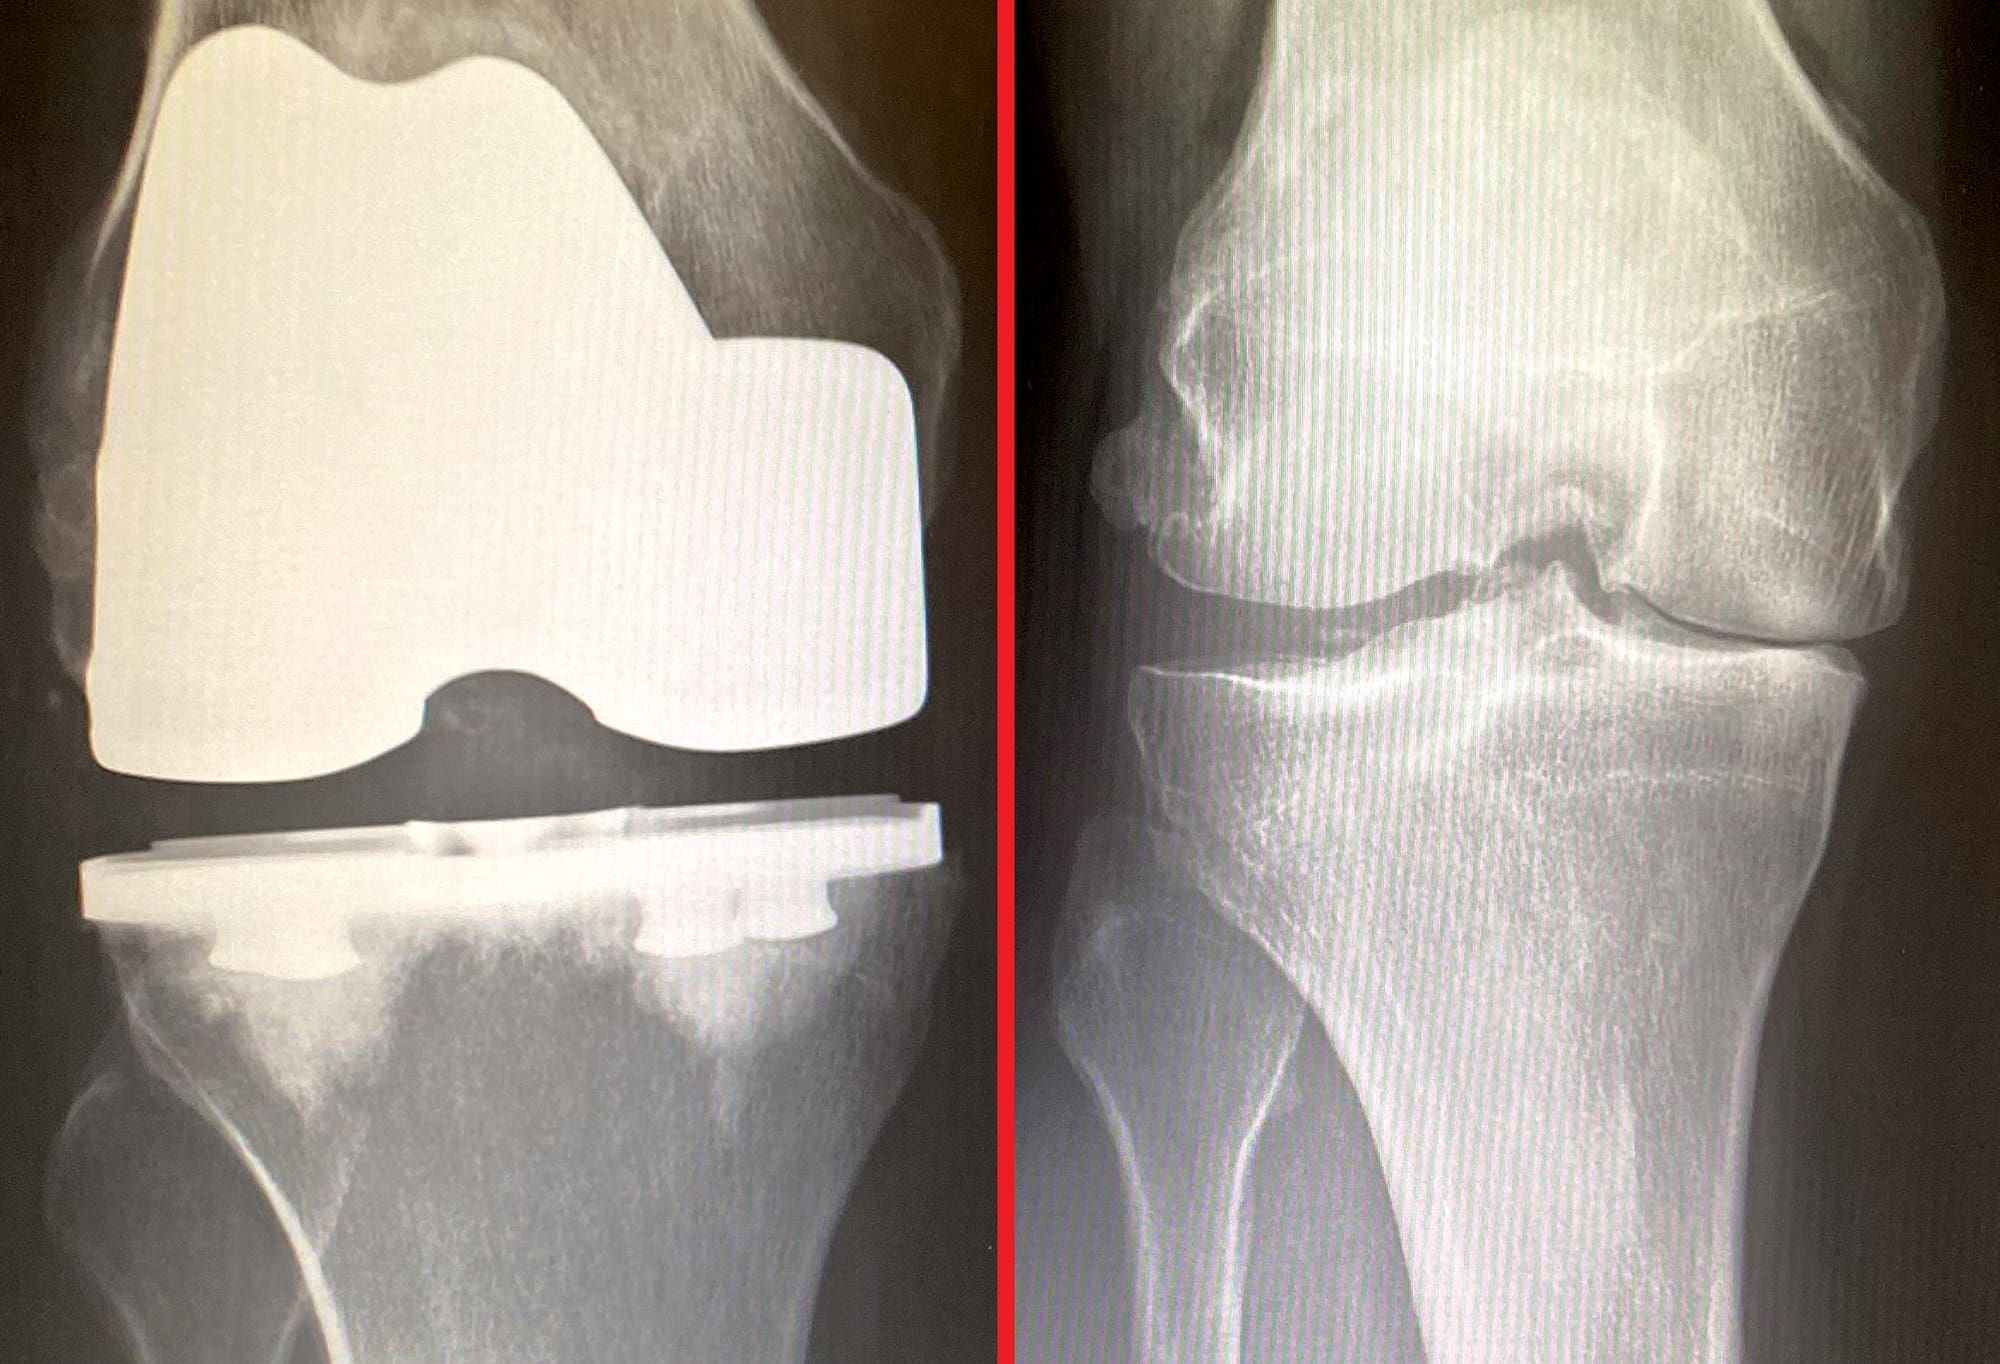

“Bottom line is, you’re going to need a knee replacement at some point,” the orthopedic surgeon told me.

“When do you think I’ll need one?” I asked.

“Oh, you’ll know,” was his answer.

A lifetime of having one knee weaker than the other, hard mountain hunting and compensatory movements took their toll. By the time I was 50, my right knee was pretty worn out. Bone spurs had developed in places of torn and missing cartilage, and I was digressively losing range of motion and experiencing a tightening hamstring. Cortisone shots had lost effectiveness, and the pain in my knee was impacting my quality of life.

I experienced a great deal of mental apprehension with the choice to undergo knee replacement. This surgery was a one-way door and there was no going back. If it didn’t work as advertised, my career was over, and my life would be forever changed. Yes, success rates are high for knee replacement surgery, but for 100% success, they are not.

On March 19th of 2021, I lay on an operating room table, cracking jokes and using humor to deflect the stress I felt. Less than two hours later, I was waking up, disoriented somewhat, having zero sense of time passed. Pharmacology was working wonders, I was in no discomfort, and the amazing Dr. Jared Foran told me everything went great, with no complications. By 7 PM that evening, Shellie was pulling our GMC up to the doors of Colorado Ortho Surgery center and I was walking, very gingerly, out the doors of the hospital, just a few hours after having my leg filleted open, bones drilled and sawed upon, and a new, titanium knee joint glued into place.